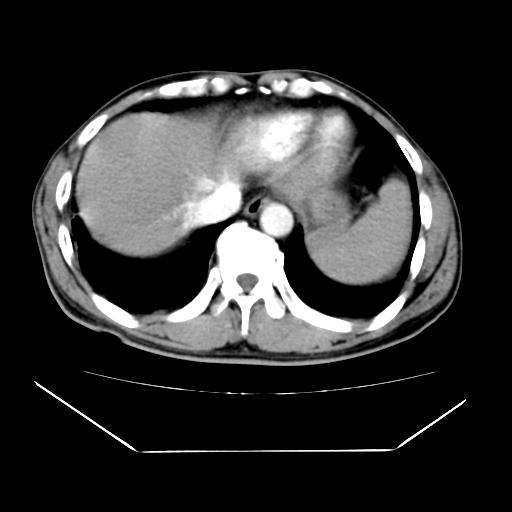

男性,55岁,外院体检afp明显升高,但b超未发现异常,否认乙肝病史。来我院ct增强。有延时扫描。

延时扫描完全充填,血管瘤

肝脏右叶动脉期可见低密度影,至延迟期被充填,考虑血管瘤可能性大。

不排除肝右叶肝癌可能。

如果这个是癌灶的话则下腔静脉有瘤栓可能

肝6段血管瘤

血管瘤可能性大。

考虑肝右静脉影。